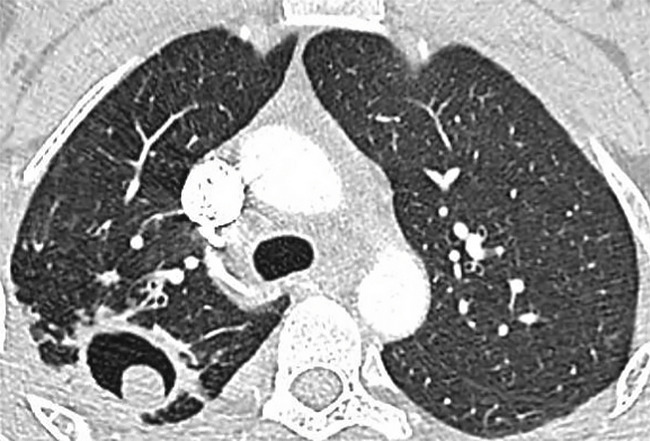

L’aspergillome simple (AS ; fig. 2) a l’aspect d’une balle fongique constituée d’hyphes siégeant dans une cavité pulmonaire ou pleurale préexistante ou, plus rarement, dans un foyer de dilatation bronchique. À la radio, c’est initialement un simple épaississement de la surface interne d’une cavité à paroi fine, habituellement au niveau des lobes supérieurs. Aspect typique : image arrondie intracavitaire déclive entourée d’un croissant gazeux.4 L’AS touche des patients immunocompétents. Les manifestations pulmonaires sont rares et discrètes, elles sont liées à l’érosion de la paroi de la cavité par la balle qui peut provoquer une hémoptysie massive.

Contrairement à l’AS, dont la prise en charge est avant tout chirurgicale, l’APC (fig. 3) requiert généralement un antifongique systémique prolongé au moins 6 mois,4 avec parfois un geste chirurgical. Un antifongique à long terme expose aux risques d’interactions médicamenteuses, d’événements indésirables et de résistance.